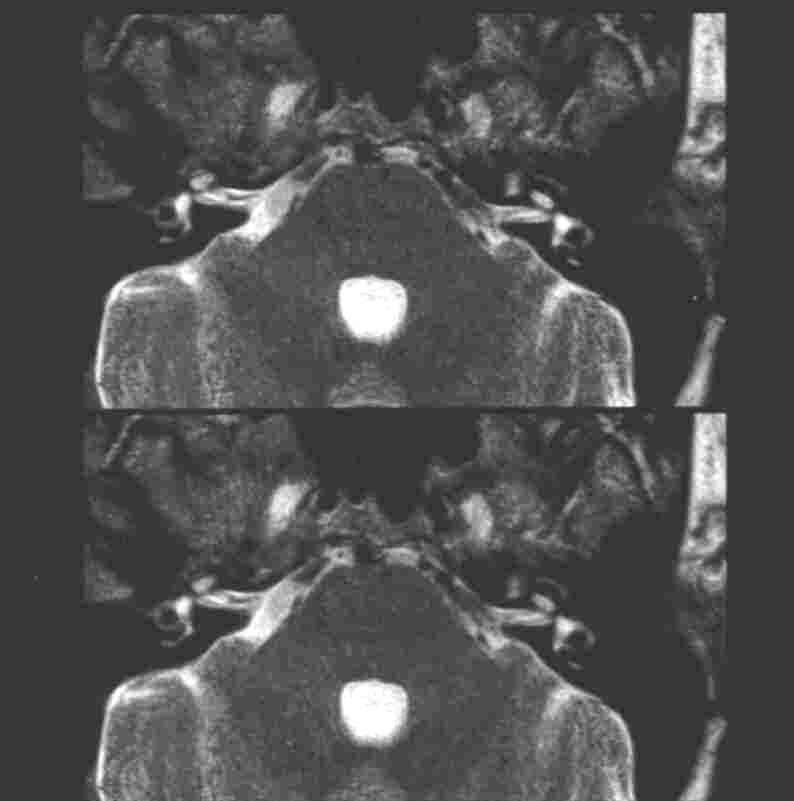

MRT Kleinhirnbrückenwinkel

An den Sinnesorganen können Störungen des Riech-, Seh- und Hörnervs sowie zunehmend auch des Gleichgewichtsorgans beurteilt werden.